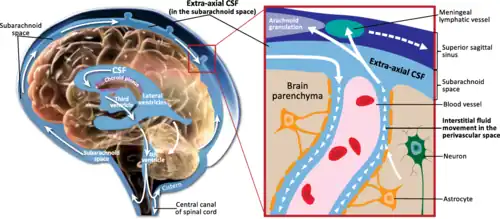

| Circulation of CSF | |

| The meninges of the central nervous system impacted by CSF leak | |

A cerebrospinal fluid leak (CSF leak or CSFL) is a medical condition where the cerebrospinal fluid (CSF) that surrounds the brain and spinal cord leaks out of one or more holes or tears in the dura mater.[1] A CSF leak is classed as either spontaneous (primary), having no known cause (sCSF leak), or nonspontaneous (secondary) where it is attributed to an underlying condition.[2][3] Causes of a primary CSF leak are those of trauma including from an accident or intentional injury, or arising from a medical intervention known as iatrogenic. A basilar skull fracture as a cause can give the sign of CSF leakage from the ear, nose or mouth.[4] A lumbar puncture can give the symptom of a post-dural-puncture headache.

Cerebrospinal fluid is produced by the choroid plexus in the ventricles of the brain and contained by the dura and arachnoid layers of the meninges.[23][42][64] The brain floats in CSF, which also transports nutrients to the brain and spinal cord. As holes form in the spinal dura mater, CSF leaks out into the surrounding space. The CSF is then absorbed into the spinal epidural venous plexus or soft tissues around the spine.[24][65] Due to the sterile conditions of the soft tissues around the spine, there is no risk of meningitis.[24]